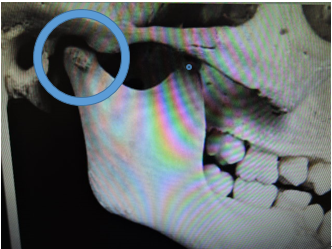

0歳時のときは顎関節がありませんでしたが、第一乳臼歯が萌えてくる時期になると、平らだった顎関節の骨に1年ほどで関節状の凹みが出来始めます。

この凹みによって顎を動かす事が出来るようになります。

0歳時のときは顎関節がありませんでしたが、第一乳臼歯が萌えてくる時期に下の写真の様に平らだった骨が1年ほどで関節状の凹みが出来始めます。